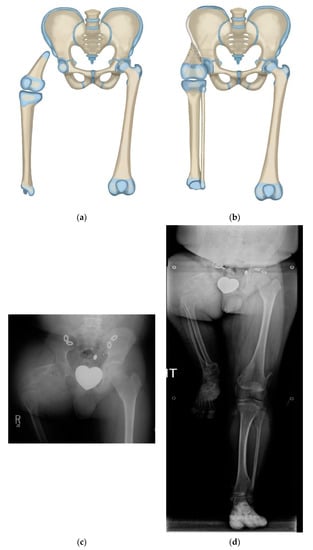

Figure 2.

(a) Illustration of CFD Paley type 3 (a or b), (b) Illustration after Brown rotationplasty for Paley type 3 (a or b), (c) AP pelvis x-ray of 14-year-old boy with Paley type 3b CFD, (d) Preop standing erect leg x-ray of same boy, showing that the ankle is at the level of the opposite knee (incidentally this patient also has multiple osteochondromas), (e) AP pelvis radiograph in same boy, 7 years after healed Brown rotationplasty, (f) Sanding radiograph with prosthetic 7 years after Brown rotationplasty with supramalleolar osteotomy for ankle realignment. Clinically he has excellent gait and function.